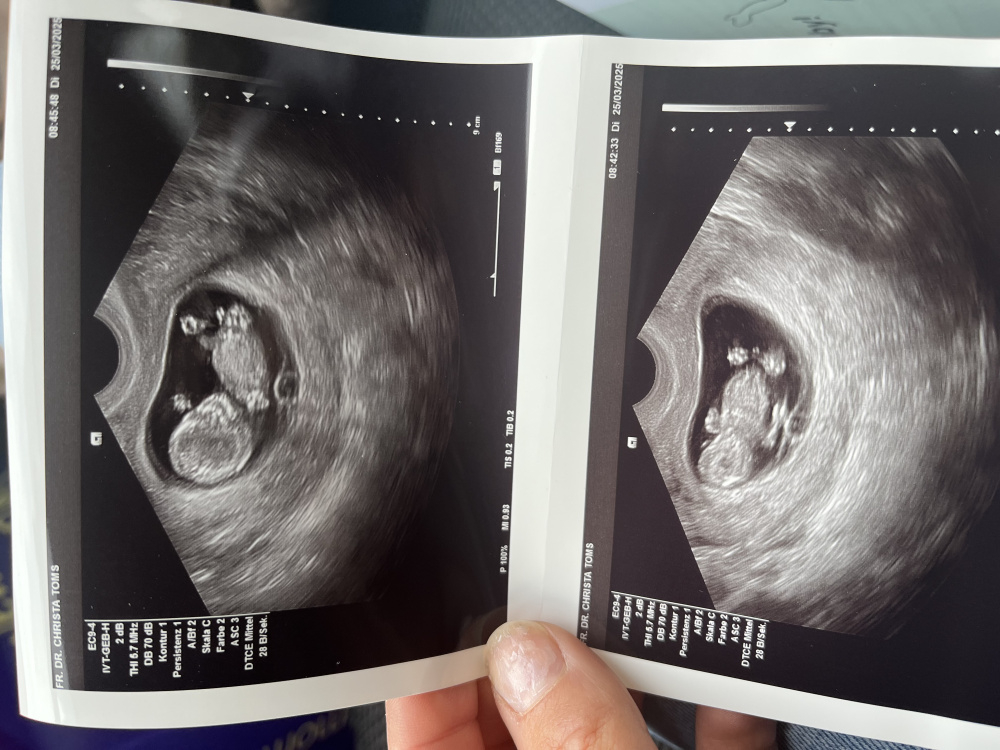

Hallo zusammen, ich war bei SSW 12+2 beim ETS. Ich habe einige Bilder erhalten. Leider bin ich sehr schlecht beim Erkennen von Ultraschallbildern. Könnt ihr mir helfen und erklären, was ich da sehe? Allen einen schönen Sonntag 🌻

Hallo zusammen👋🏻

War heute beim US (12+5) und bin mir nicht sicher: Ist das überhaupt der NUB und wenn ja, was würdet ihr sagen, was es wird?

Danke schon mal im Voraus 😊